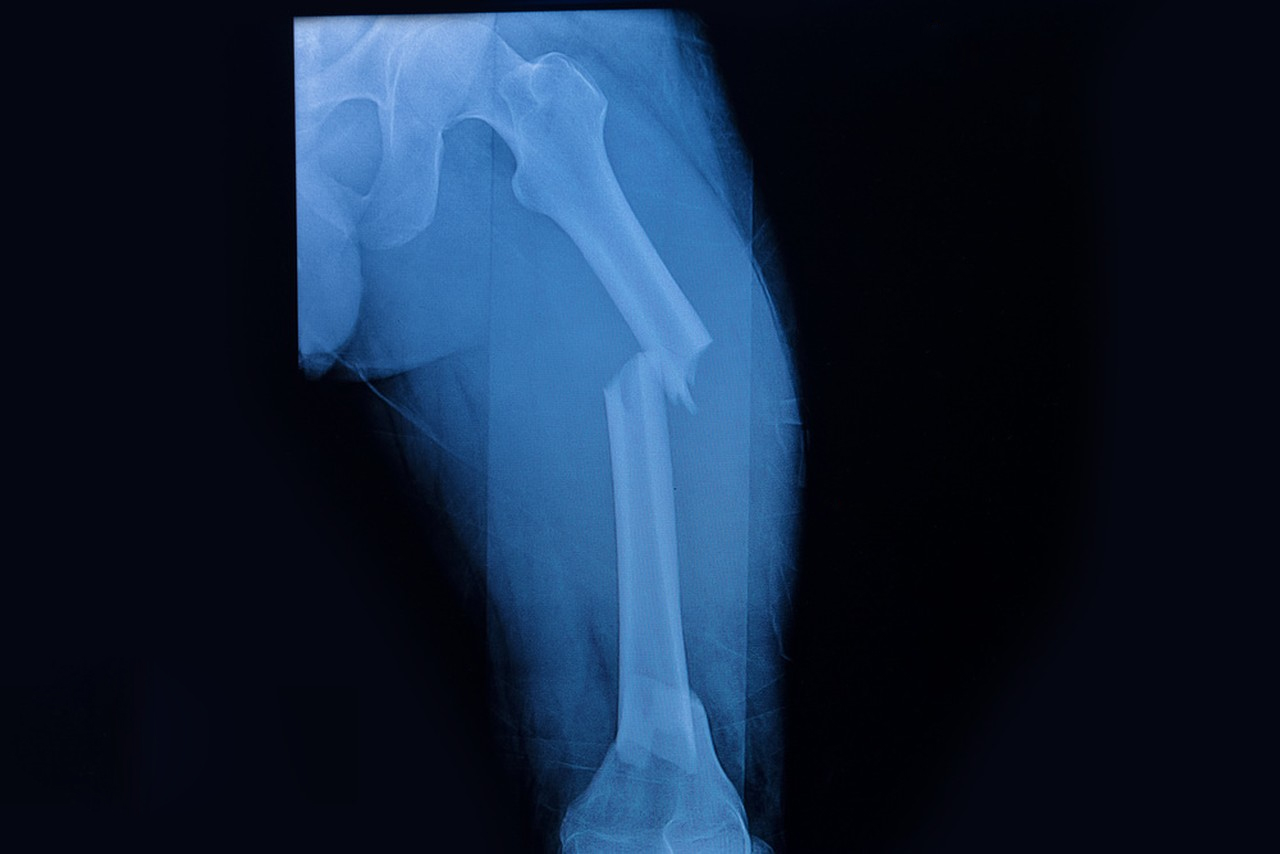

骨折的急性期主要是指嚴重的骨折或開放性骨折,如骨盆骨折、股骨骨折、骨折刺穿皮膚等?;颊呖赡軙霈F(xiàn)休克、大出血等癥狀。

持續(xù)牽引適用于頸椎骨折脫位、股骨骨折、脛骨骨折。